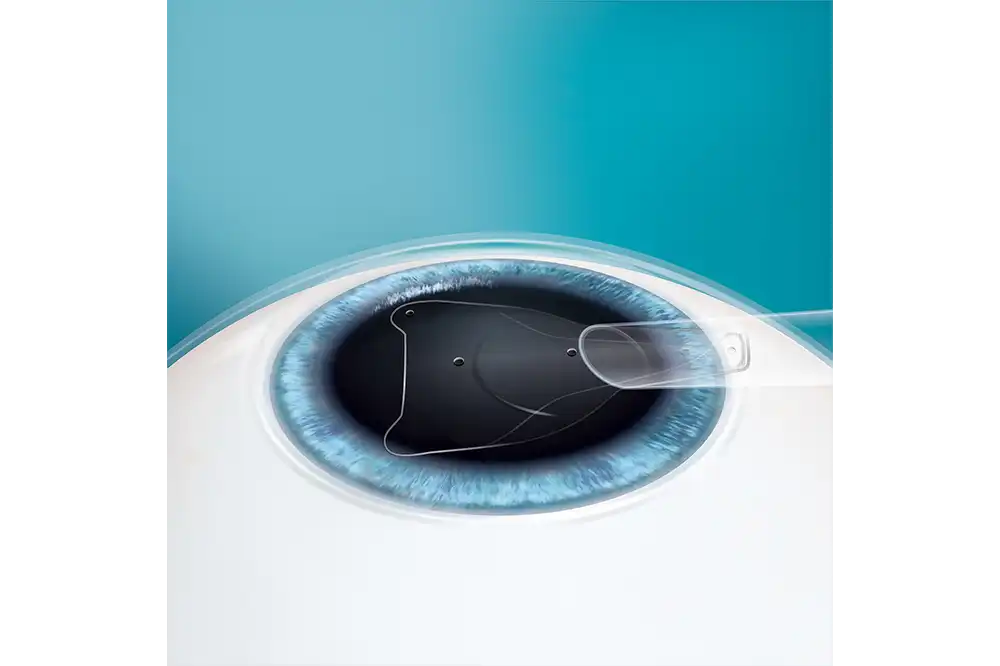

- EVO ICL is een phake lens.

- EVO wordt direct achter de iris en vóór de natuurlijke kristallijne lens geplaatst.

- De toevoeging van de centrale aqua port bij EVO vergemakkelijkt de stroom van aqueous humor doorheen de lens.

- De EVO ICL-procedure vereist geen verwijdering van corneaweefsel.

- De EVO-lens is een reversibel implantaat.